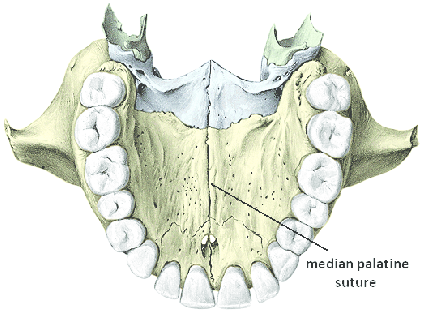

What is the median palatine suture?

Median palatine suture: The bony union where the right and left palatine processes of the maxilla fuse in the midline.

• Location: Runs along the center of the hard palate, beneath the median palatine raphe.

<p><strong>Median palatine suture: </strong>The <strong>bony union</strong> where the right and left palatine processes of the maxilla fuse in the midline.</p><ul><li><p>Location: Runs along the center of the hard palate, beneath the median palatine raphe.</p></li></ul><p></p>